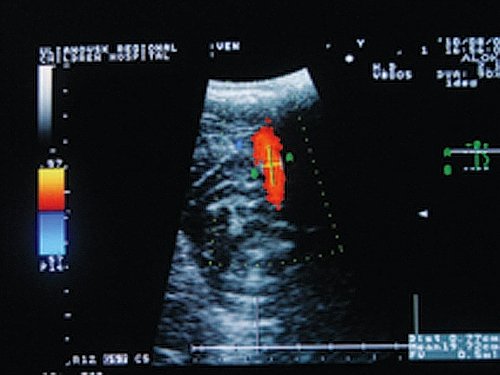

При исследовании ПС в положении лежа в покое в группе с КФП определены статистически значимо более высокие по сравнению с ГК показатели кровотока (рис. 3).

Рис. 3. Кровоток по прямому синусу у больного с конституциональной флебопатией.

У НФ эти показатели были сопоставимы с таковыми в ГК (рис. 4).

Повышение фоновых показателей ЛСК по ПС в группе с КФП является одной из составляющих допплерографического паттерна недостаточности венозного оттока из полости черепа и свидетельствует о включении путей коллатерального венозного оттока [12]. При проведении пробы Вальсальвы наблюдались разнонаправленные реакции. В ГК скоростные показатели возрастали, что свидетельствует о включении механизмов ауторегуляции мозгового кровообращения и активации путей коллатерального венозного оттока. У больных гипертонической энцефалопатией независимо от наличия конституциональной венозной недостаточности скоростные показатели снижались, что опять же свидетельствует о неадекватном функционировании механизмов ауторегуляции мозгового кровообращения.